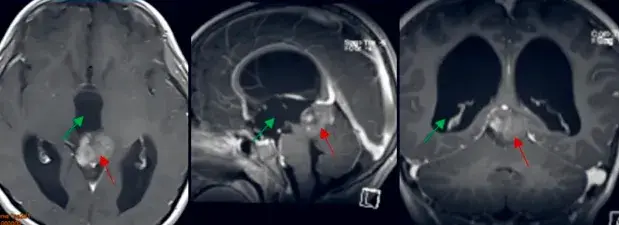

脑干胶质瘤(BSG)手术难度巨大,大多治疗以综合为主,包括手术、放化疗、基因靶向治疗以及免疫治疗等新疗法。手术可显著改善外生型及局灶型低级别肿瘤的预后,尤其对于毛细胞星形细胞...

一开始孩子只是爱摔倒,谁曾想后来竟然恶化到偏瘫了! 一想到6岁的女儿以后很可能不良于行,身为母亲的吴女士满心懊悔:当初没有医生告诉我们能安全手术的,这个脑干胶质瘤手术风险太...